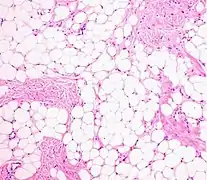

A lipoma is a benign tumor made of fat tissue.[1] They are generally soft to the touch, movable, and painless.[1] They usually occur just under the skin, but occasionally may be deeper.[1] Most are less than 5 cm (2.0 in) in size.[2] Common locations include upper back, shoulders, and abdomen.[4] It is possible to have a number of lipomas.[3]

A physical exam is typically the easiest way to diagnose it. Rarely, a tissue biopsy or imaging may be required. The imaging modality of choice is magnetic resonance imaging (MRI) because it has superior sensitivity of distinguishing it from liposarcoma as well as mapping the surrounding anatomy.[22]

Usually, treatment of lipomas is not necessary, unless they become painful or restrict movement. They are usually removed for cosmetic reasons if they grow very large or for histopathology to verify that they are not a more dangerous type of tumor such as a liposarcoma.[13] This last point can be important, as the characteristics of a tumor are not known until after it is removed and medically examined.